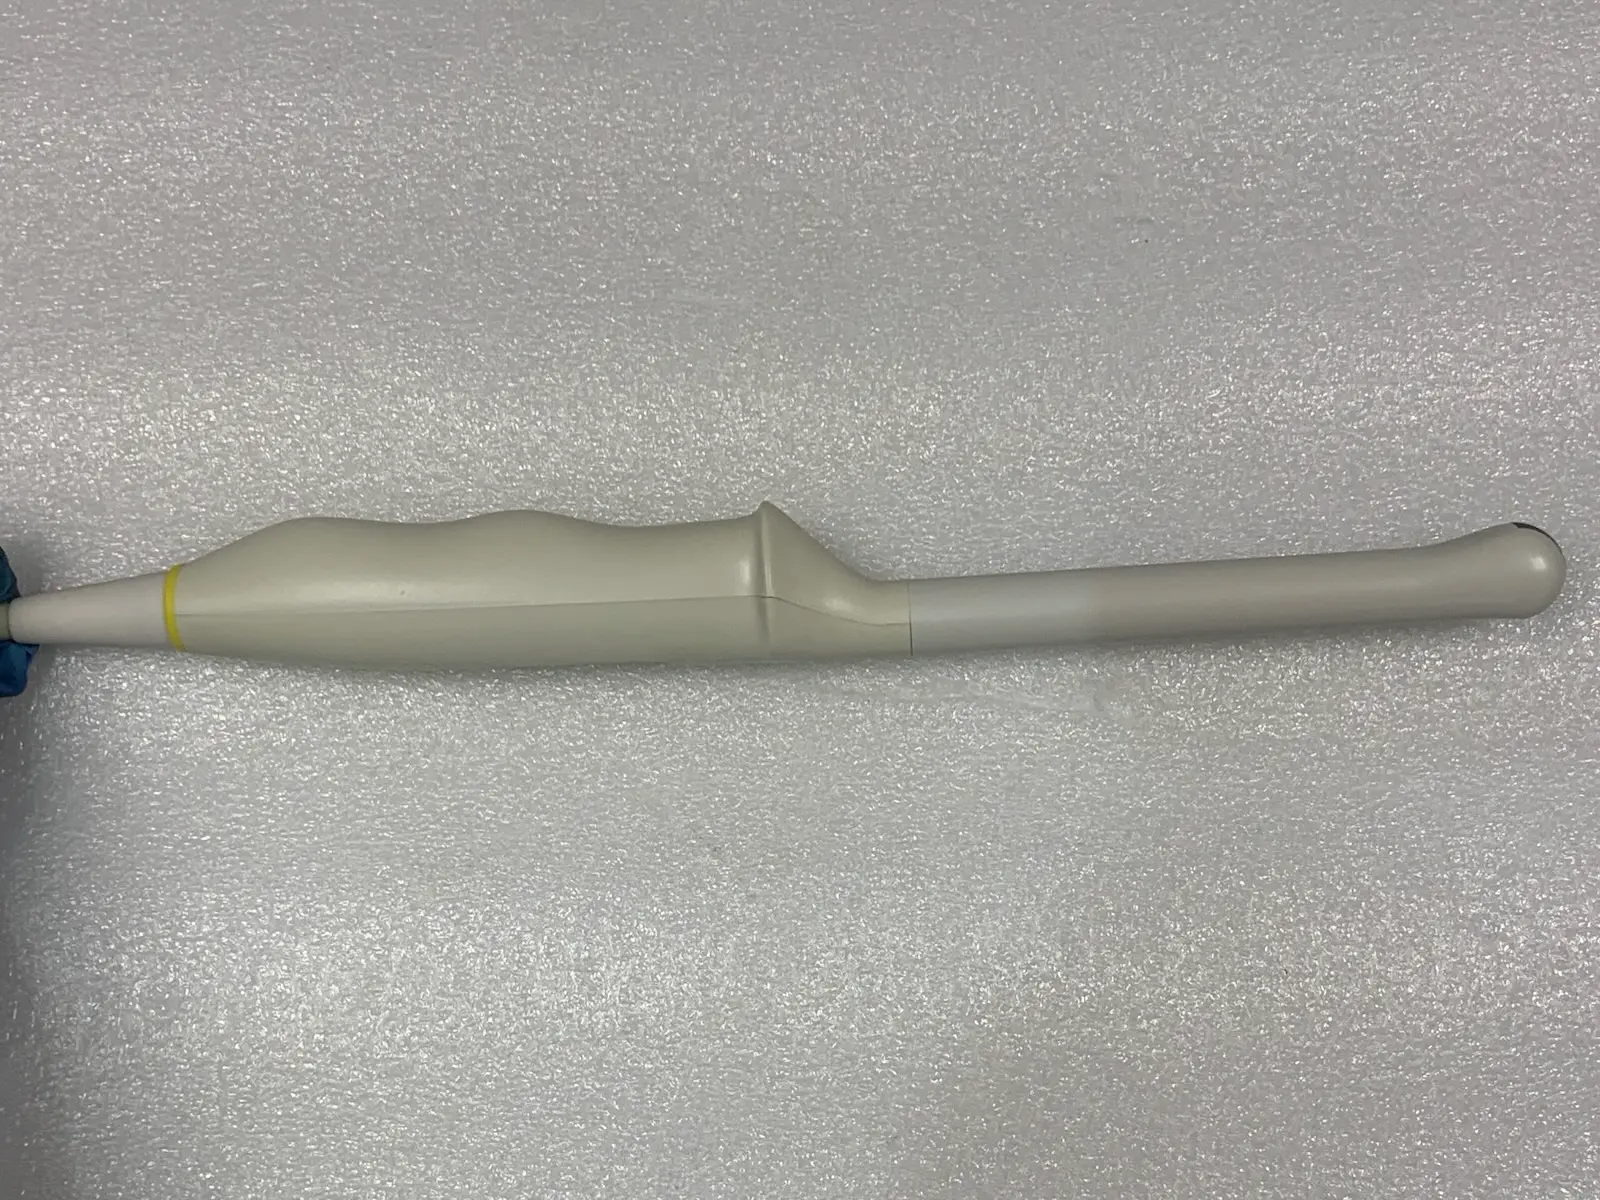

Up for sale is a genuine Mindray V10-4s curved array endocavity probe. This transducer is designed for high-resolution imaging in obstetrics, gynecology, and urology. It features a wide-band frequency range (4–10 MHz) and a small 10mm radius for patient comfort.

Acoustic Window (Lens): Appears clean and intact with no significant delamination or pitting visible in photos.

Blemish : Some cosmetic blemishes

Photos of this listing are of the actual item for sale.